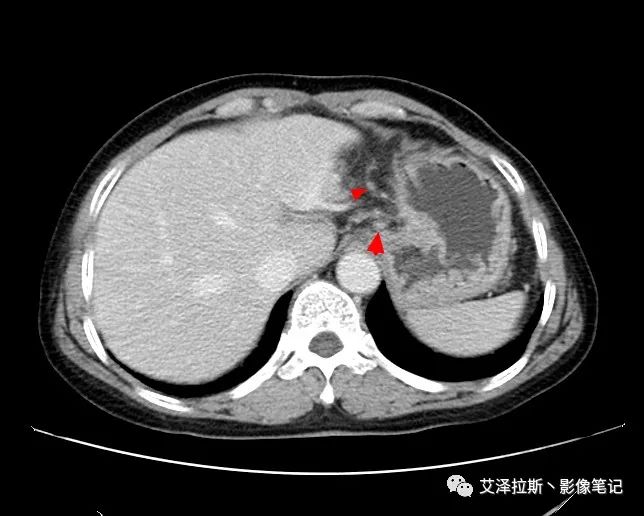

【影像所見】 胃竇部狹窄,胃壁環形增厚,小彎側見一巨大潰瘍,周圍伴“環堤征”,漿膜面不完整,胃周脂肪見網格狀條索影,病灶與肝臟左葉、胰腺鉤突脂肪間隙消失,增強掃描病灶明顯強化。引流區內約15個區域淋巴結受累。

【診斷意見】 胃竇部胃癌(T4N3期) 該病例腫塊突破漿膜層,與肝臟左葉、胰腺鉤突分界不清,脂肪界面消失,定為T4期; 受累及的淋巴結為15個區域,定為N3; 有無遠處轉移尚不明確,所以M期暫時無法確定。